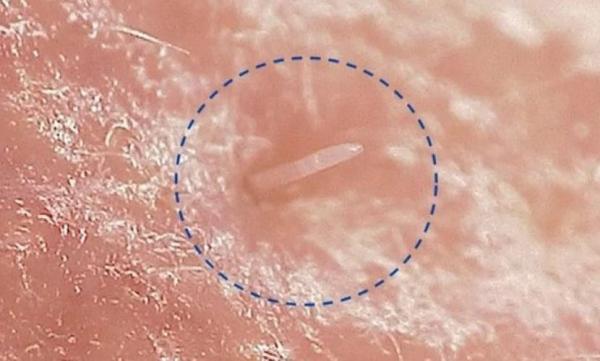

• Передлежання плаценти - перекриття шляхів виходу для дитини плацентою. Цю ситуацію видно на УЗД, тому це не буде несподіванкою, крім того часто до останнього терміну вагітності плацента як би підводиться і «передлежання» проходить;